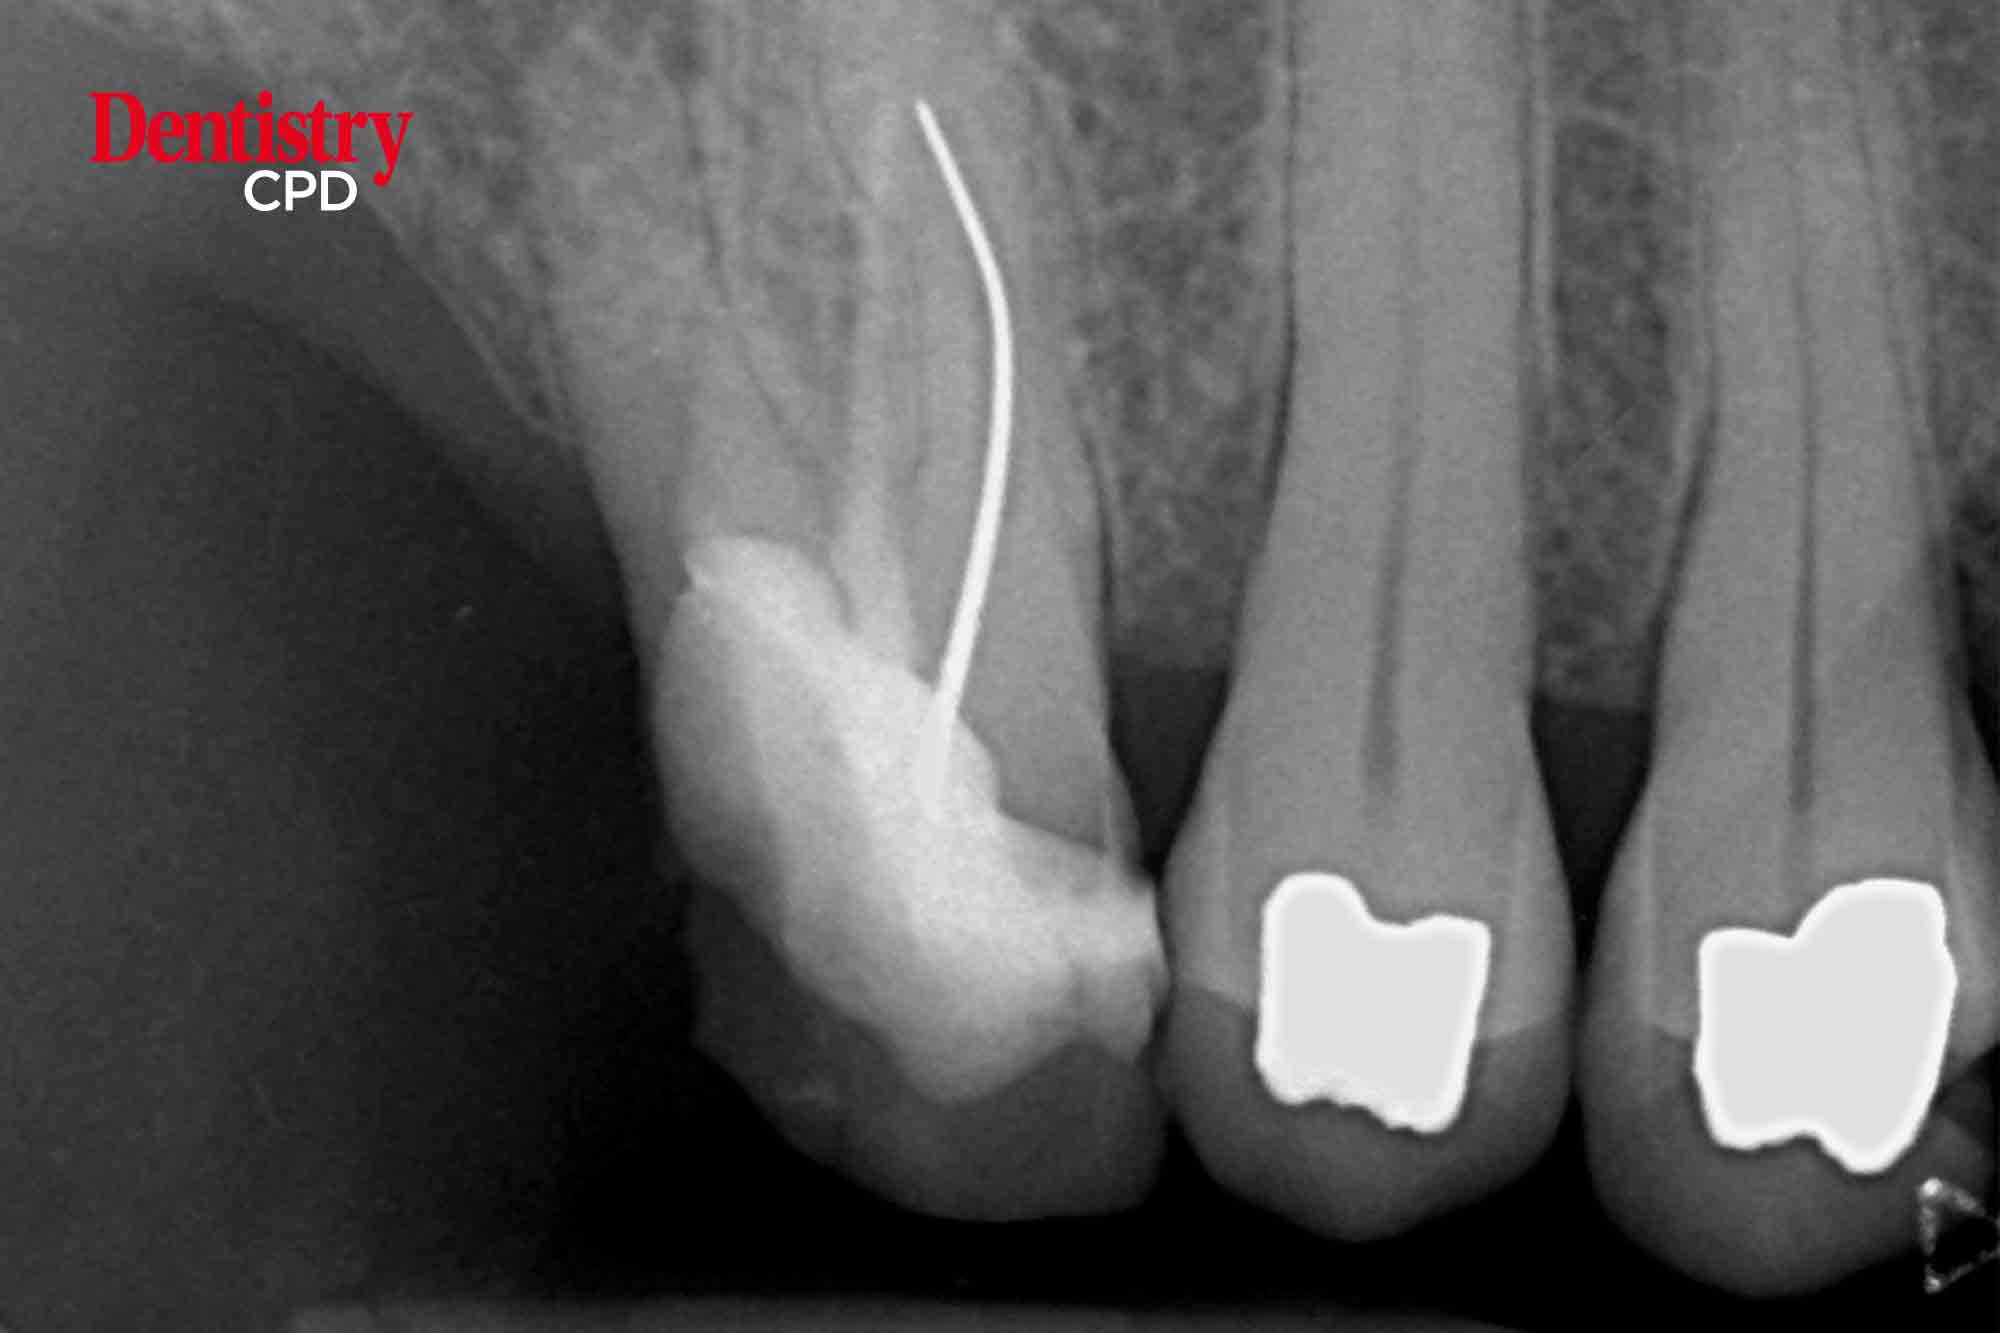

John Rhodes presents another practical and problem-solving solution in endodontics. This time he looks at how root canal morphology can be used advantageously during non-surgical root canal retreatment